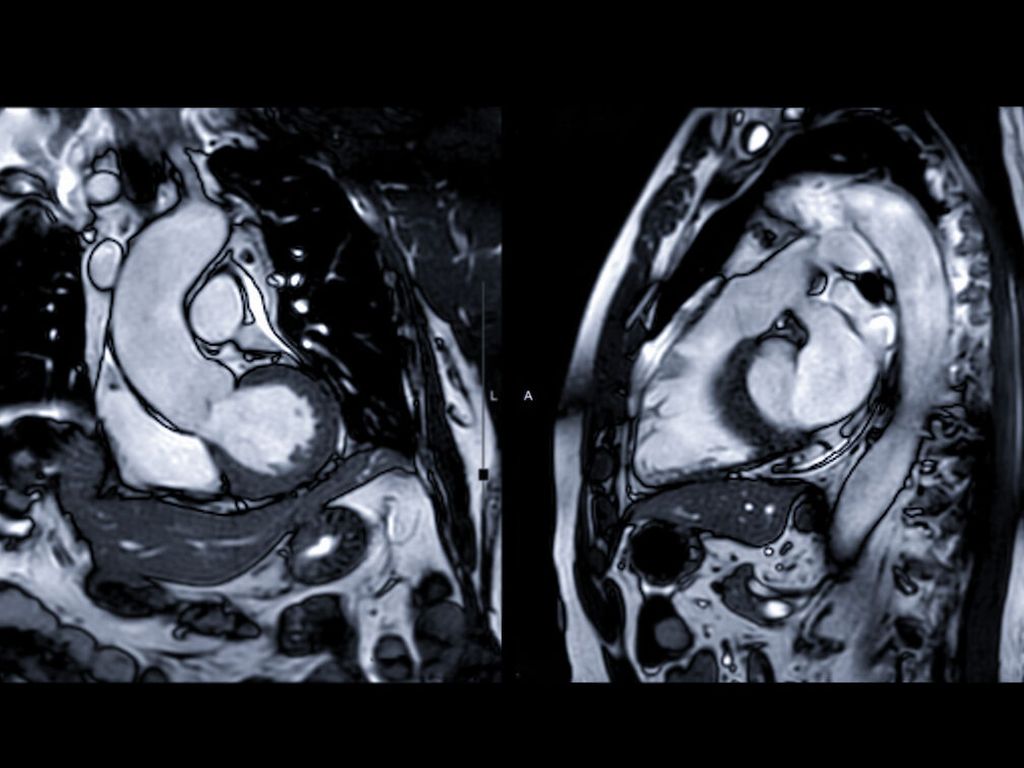

Die Behandlung des Mantelzelllymphoms im Fokus neuer Therapieoptionen